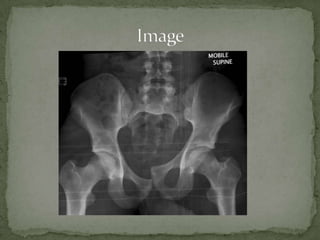

A 33-year-old male construction worker presented with extreme pain in his right pelvis and lower back after falling 20 feet from scaffolding and landing on his fully extended right leg. He was tachycardic and diaphoretic. Examination found his right leg shortened with pain on range of motion and blood at the urethral meatus. Imaging revealed significant hemorrhage into the retroperitoneum likely from branches of the internal iliac artery, superior gluteal artery, or sacral venous plexus. He received intravenous fluids, oxygen, and a trauma workup. An orthopedic consult was emergently placed for possible unstable pelvic fractures requiring angiography.